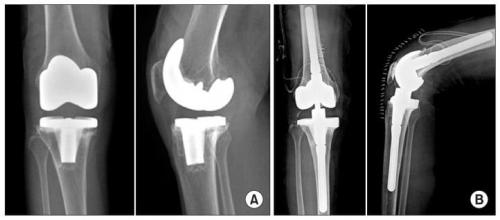

Частота инфекционных осложнений после хирургического вмешательства составляет 0,2-4,5% при первичном протезировании и 4,5-12% при ревизионном (повторном).

Развитие гнойно-воспалительных осложнений в первые 12 месяцев обусловлено микробной контаминацией во время хирургического вмешательства. Патогенные микроорганизмы могут проникать в коленный сустав аэрогенным или контактным путем. Они заносятся в рану с грязным воздухом, руками хирурга или хирургическим инструментарием.

Риск послеоперационных осложнений особенно высок у пожилых людей больных с сахарным диабетом , ожирением , ревматоидным артритом , иммунодефицитными состояниями и у пациентов принимающих кортикостероиды. Прогноз также ухудшают небольшой опыт оперирующего хирурга, большая кровопотеря, длительность операции свыше 3 часов и применение костного цемента без антибиотика в составе.

В более позднем периоде (спустя год и более после операции) воспалительные осложнения являются следствием гематогенного распространения микроорганизмов. Патогенные микробы проникают в суставную полость с током крови из очагов хронической инфекции.

Выраженность клинических проявлений у больного зависит от источника инфицирования, вирулентности возбудителя и времени развития патологии. Классическая яркая картина гнойного воспаления (лихорадка, отек и гиперемия колена, образование свища ) наблюдается менее чем у половины пациентов. Остальных могут беспокоить постоянные боли в коленном суставе, которые усиливаются при движениях.

Для успешной борьбы с парапротезной инфекцией требуется комплексный подход. Наиболее эффективной является открытая санация суставной полости с полным удалением всех составляющих протеза (сохранение любого из компонентов импланта в итоге может привести к повторному хирургическому вмешательству). Вместе с этим больному назначается локальная антибиотикотерапия путем создания депо в воспалительном очаге.

Слева имплант после первичной операции, справа после ревизионной, он существенно больше в размерах для прочной фиксации.

Консервативное лечение инфекционных осложнений возможно лишь при ранней диагностике, низкой вирулентности возбудителя и наличия противопоказаний к операции.